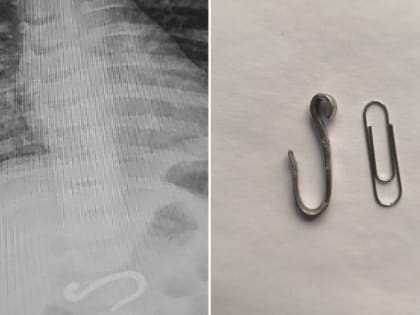

Загадочный металлический предмет в желудке младенца

В Челябинске врачи успешно извлекли крупный крюк из желудка восьмимесячного малыша.